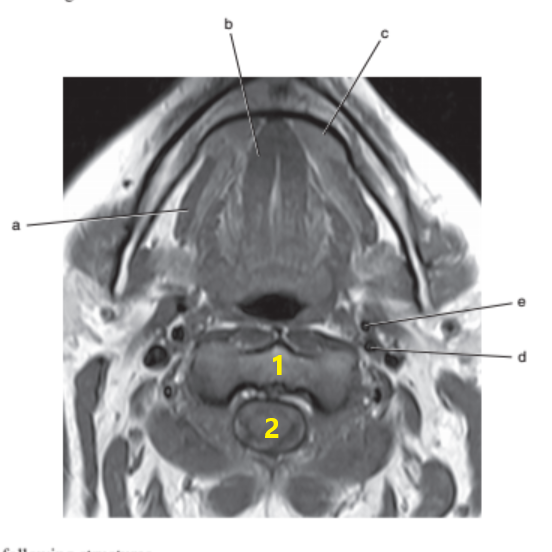

What anatomy is letter e ?

Nasopharynx

What is # 1 ?

Mandible

Tongue

What anatomy is letter b ?

Epiglottis

Soft palate

What is # 3 ?

Brain stem